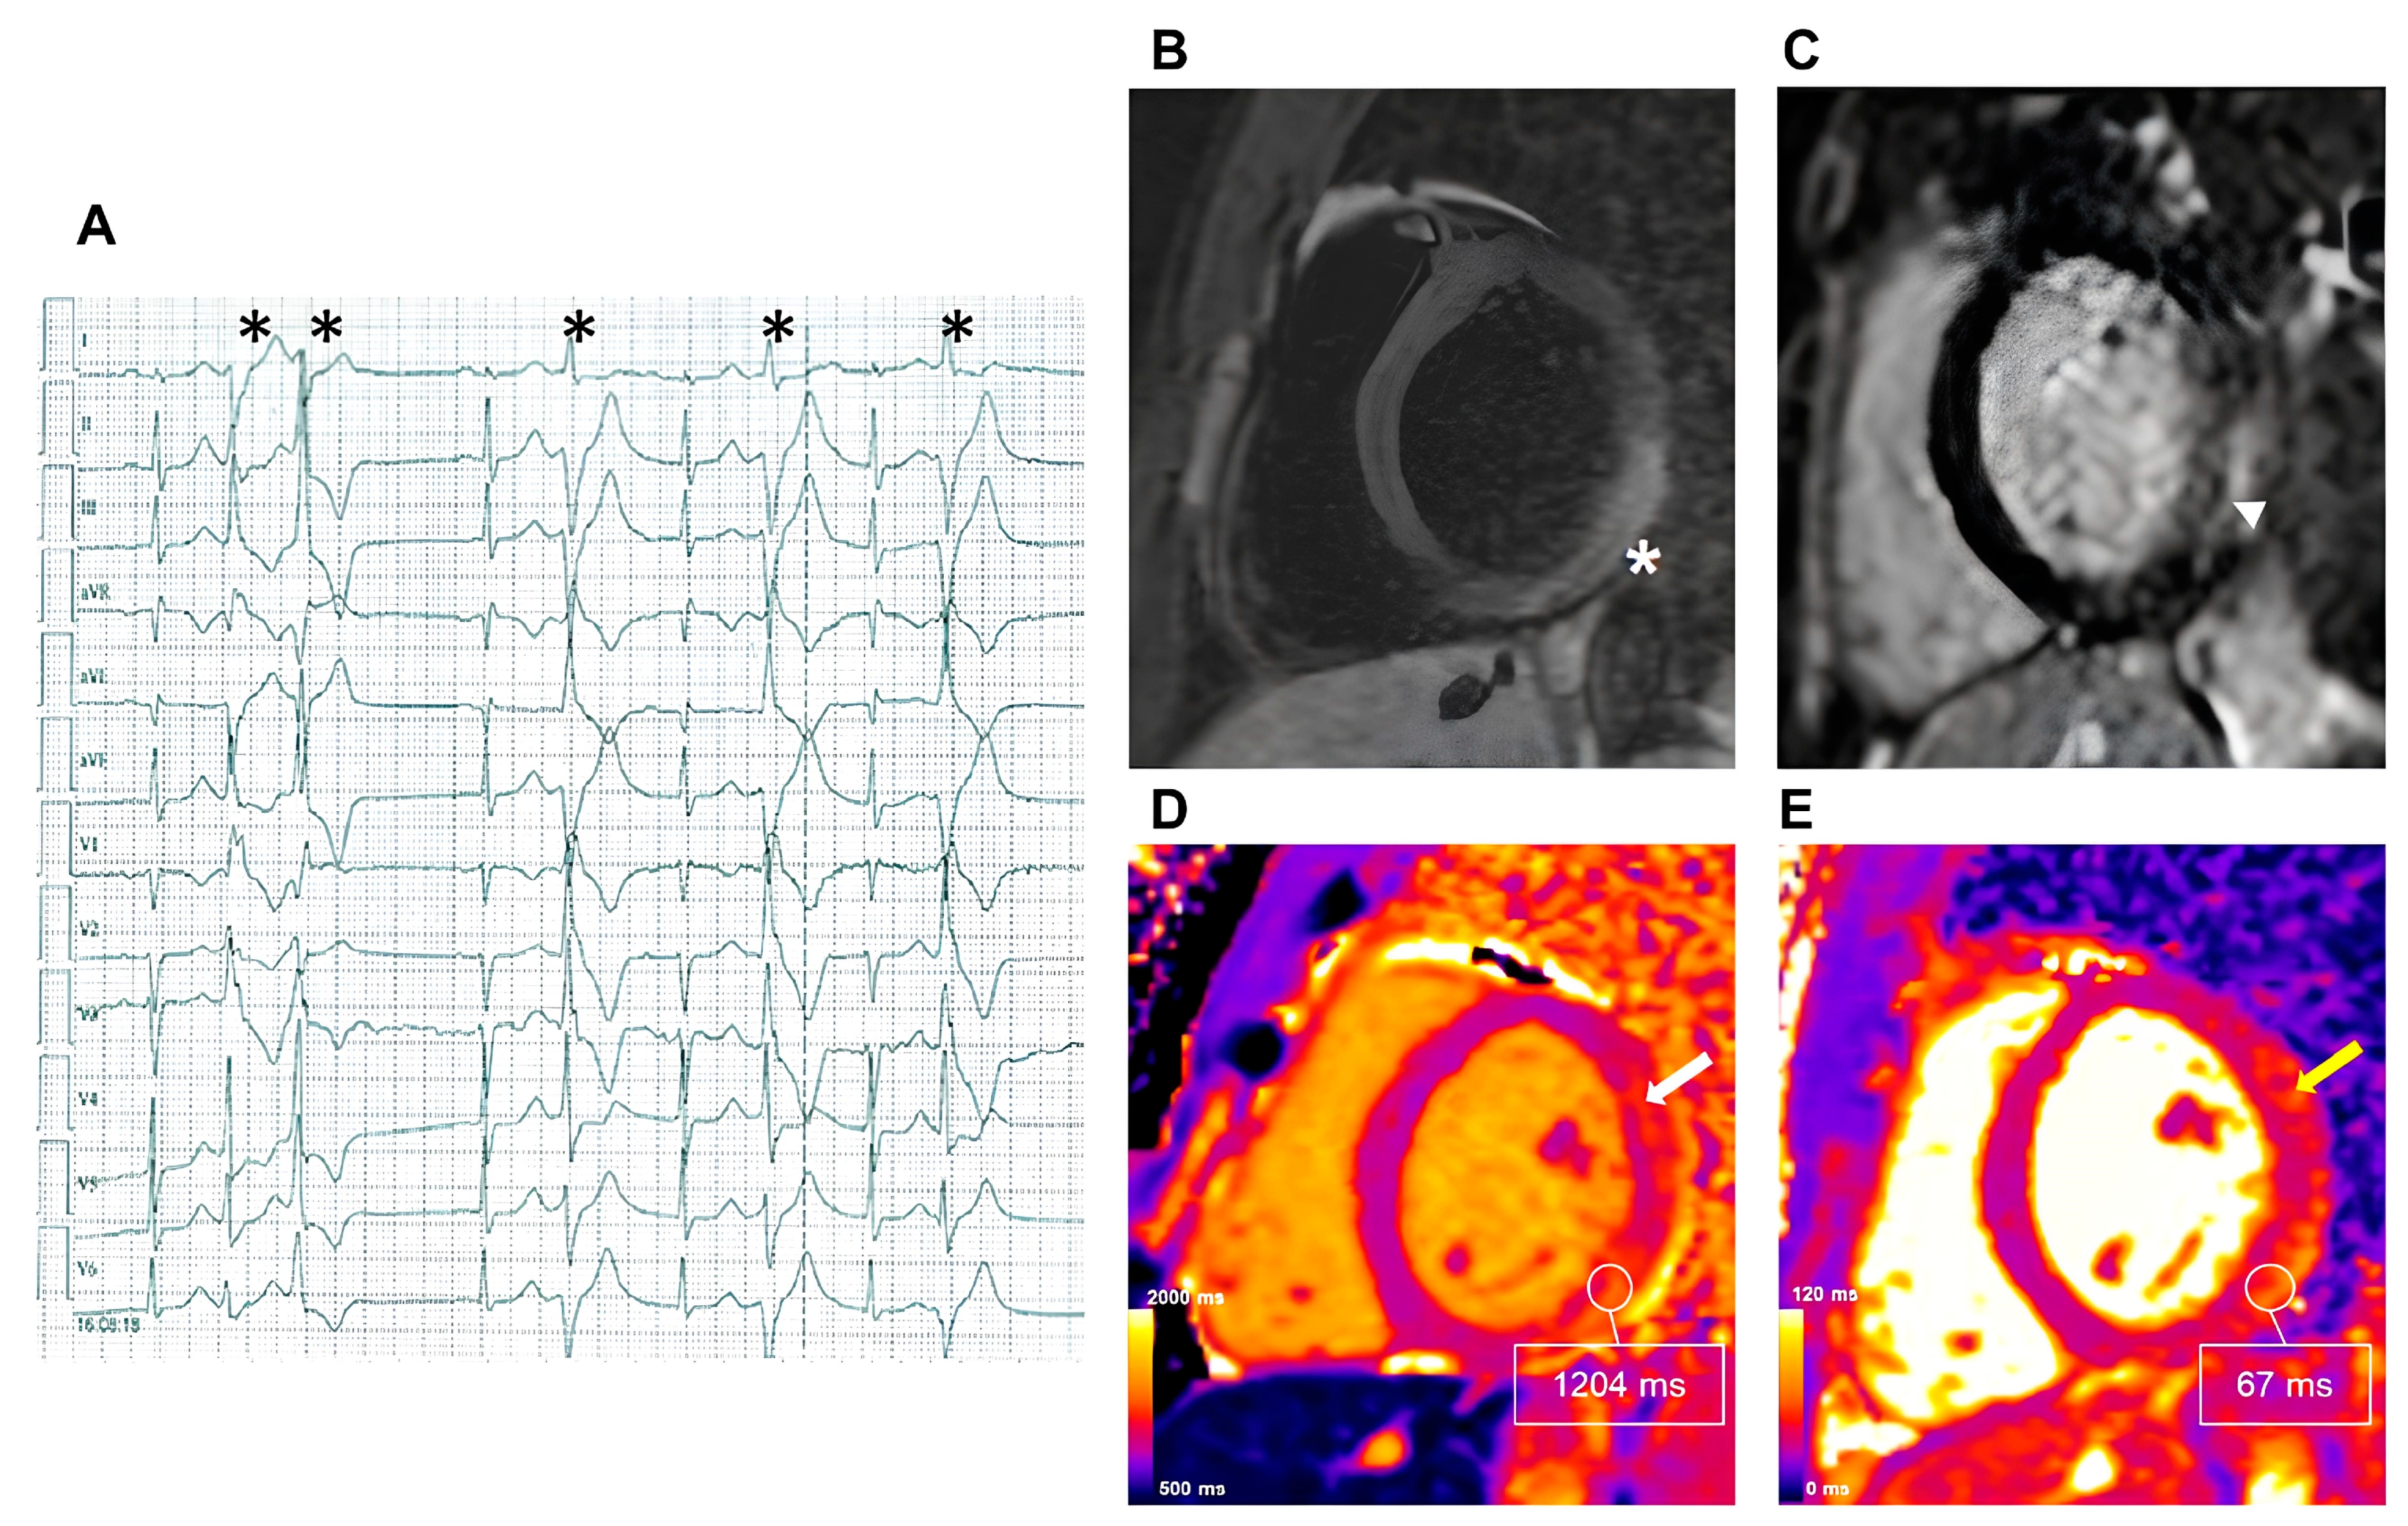

2.2.1. Myocarditis

- Gil, K.E.; Truong, V.T.; Zareba, K.M.; Varghese, J.; Simonetti, O.P.; Rajpal, S. Parametric mapping by cardiovascular magnetic resonance imaging in sudden cardiac arrest survivors. Int. J. Cardiovasc. Imaging 2023, 39, 1547–1555. [Google Scholar] [CrossRef] [PubMed]